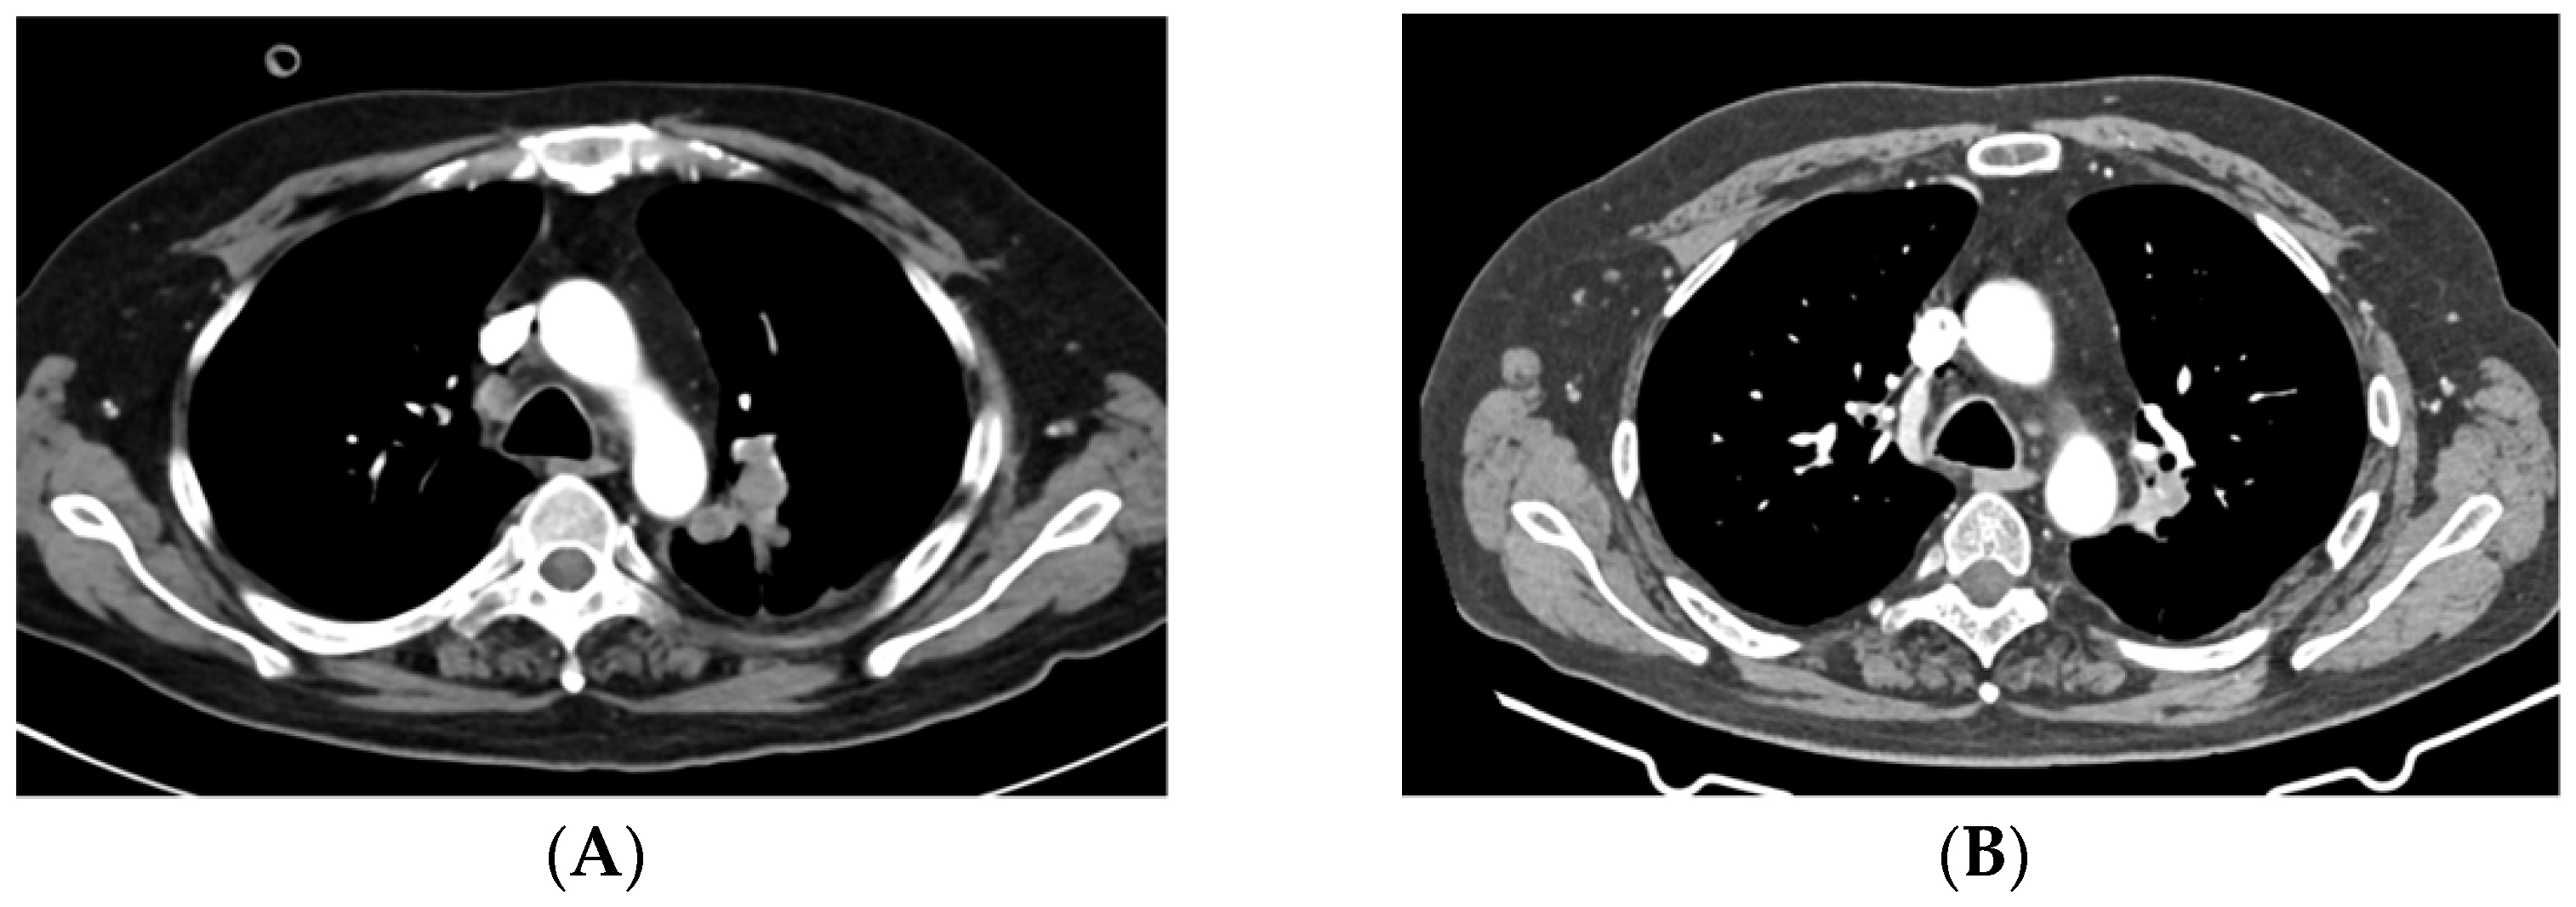

2.1. Case 1

2.2. Case 2

2.3. Case 3